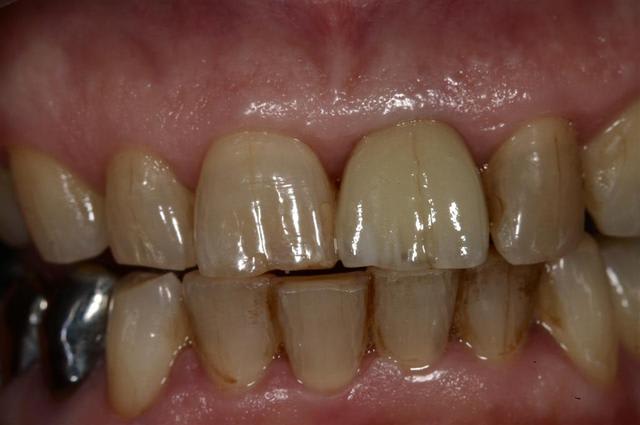

Allez, pour apporter mon caillou à la plage, un cas intéressant, d'implant en urgence.

consultation suite à une chute et fracture de 21 couronnée, un 29 Décembre, décision de poser l'implant le 31.12.

Extraction, mise en place d'un implant de 5*11.5 torque > 35N

Mise en place d'une dent provisoire transvisée.

Prothèse transvisée définitive à 3 mois.

Les 2 dernières photos à 1 an.

la photo ceram en place est à 6 mois. Noter l'amélioration des papilles entre 6 mois et 1 an...